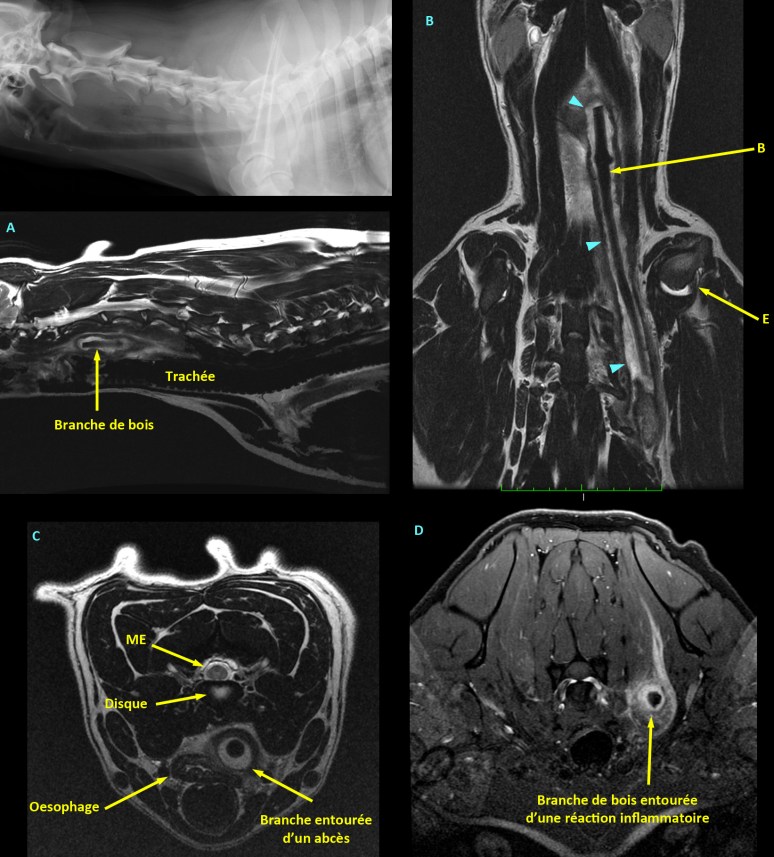

Cas intriguant 3 – Réponse

Sur les radiographies, nous avions noté d’abord un déplacement ventral et vers la droite de la trachée cervicale, de même qu’une zone hétérogène dans les tissus mous ventraux à la colonne vertébrale, associée à la présence de multiples petites bulles de gaz. Sur la VD, une opacité minérale était aussi visible médialement à l’épaule gauche, mais celle-ci s’est avérée non significative.

En raison d’une implication potentielle de la moelle épinière, nous avons opté pour l’IRM. Plusieurs séquences ont été utilisées pour mettre en valeur différents types de processus, incluant des séquences avec saturation des graisses – seulement possible avec un aimant de haut champ comme celui de la faculté – avec utilisation de milieu de contraste (gadolinium injecté IV). Sur ces images, un énorme corps étranger sans signal IRM (i.e. noir) a été identifié, entouré d’un abcès liquidien, s’infiltrant à travers les tissus mous cervicaux, depuis le plafond du pharynx jusque dans la région entre l’épaule (E) gauche et la cage thoracique, soit le plexus brachial. Ce corps étranger avait la forme d’une branche (B) et provoquait une compression et irritation des nerfs du plexus brachial gauche, expliquant ainsi les signes de boiterie à ce membre. L’image D correspond à une image transverse en pondération T1 obtenue suite à l’injection de gadolinium IV et après saturation du signal des graisses, augmentant la démarcation de la réaction inflammatoire dans cette région et ainsi que le corps étranger tout noir au centre de l’abcès. L’abcès montrait d’ailleurs une capsule hypointense bien visible sur les trois plans en pondération T2, soient sagittal (A), dorsal (B) et transverse (C). Malgré la suspicion clinique d’atteinte de la moelle épinière (ME), celle-ci était indemne sur les images. Cette composante clinique n’a donc pu être complètement expliquée.

Débile non ?!!

Un CT aurait aussi été un bon choix, mais comme une atteinte de la moelle épinière avait été initialement suspectée, l’IRM représentait une meilleure option. Sinon, l’échographie aurait aussi pu permettre de détecter le corps étranger et l’abcès au pourtour, mais l’évaluation de son étendue exacte aurait été limitée.

Cas intriguant 3 – Réponse à un commentaire

Robert faisait remarquer la forme bizarre de l’atlas (C1). En fait, cette forme est attribuée à la rotation axiale de la colonne qui déplace les ailes dorsalement/ventralement (têtes de flèches ci-bas) et qui libère le processus odontoïde (dens) qui devient alors très bien défini. Cette vue latérale alors que la tête est légèrement tournée, est fort utile lorsqu’on cherche à éliminer la possibilité de fracture ou d’hypoplasie de la dens (qui entraîne une luxation atlanto-axiale). Le problème chez ce chien se trouve ailleurs… portez attention aux tissus mous ventralement à la colonne vertébrale… Je vous raconte la suite d’ici quelques jours.

Cas intriguant 3 – Diantre, que se passe-t-il avec ce chien ?

Signalement: Labrador de 2 ans, femelle stérilisée.

Histoire clinique: Dysphagie, douleur au cou, boiterie de non appui MTG, parésie MPs pire a gauche. Lésion suspectée au niveau cervical caudal latéralisée à gauche.

Ce cas nous a tous laissés perplexes compte tenu de la présentation clinique…

Pour suite, cliquez ICI.